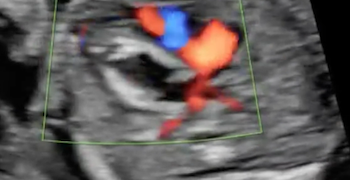

Caso del Mese di Dicembre 2021

Cari soci, finalmente la soluzione del caso del mese di Dicembre! Scarica il File L'attesa è finita: Al seguente link la...